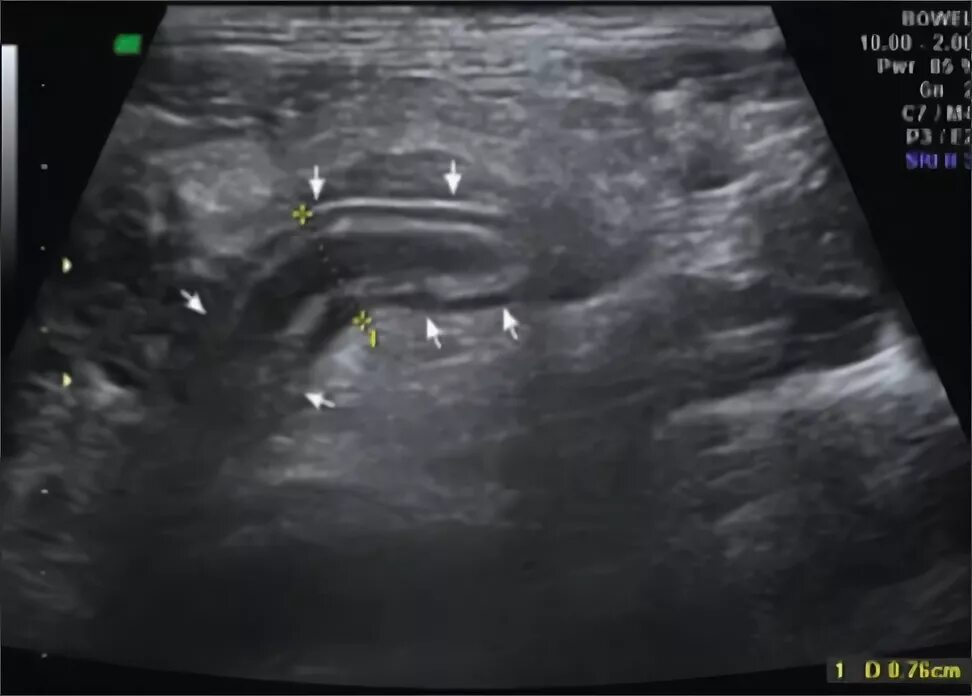

Аппендицит на узи можно ли